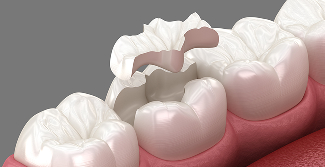

하이브리드 인레이

레진과 세라믹을 혼합한 재료로, 레진보다 강하고 세라믹보다는

유연하여 손상된 치아의 일부를 복원하는 보철 치료 방식입니다.

• 강한 소재

• 유연한 강도